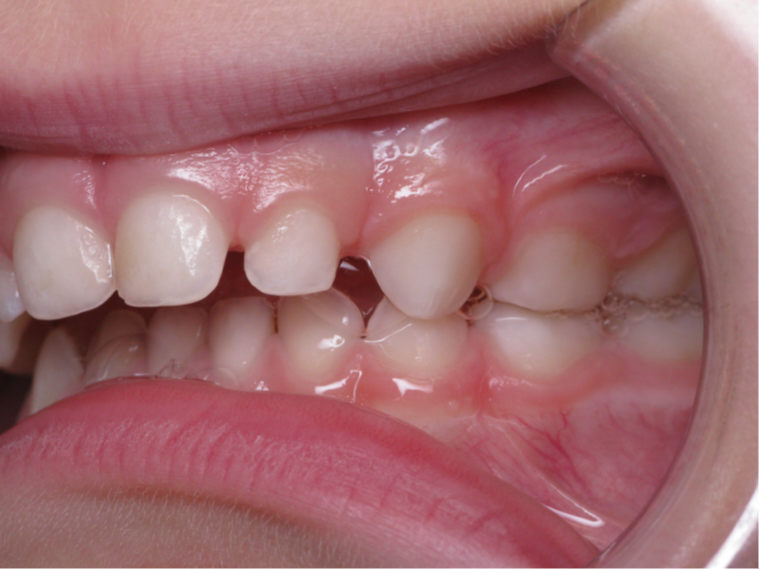

6 décalage sagittal 5 ans

Décalage entre les dents d avant en arrière